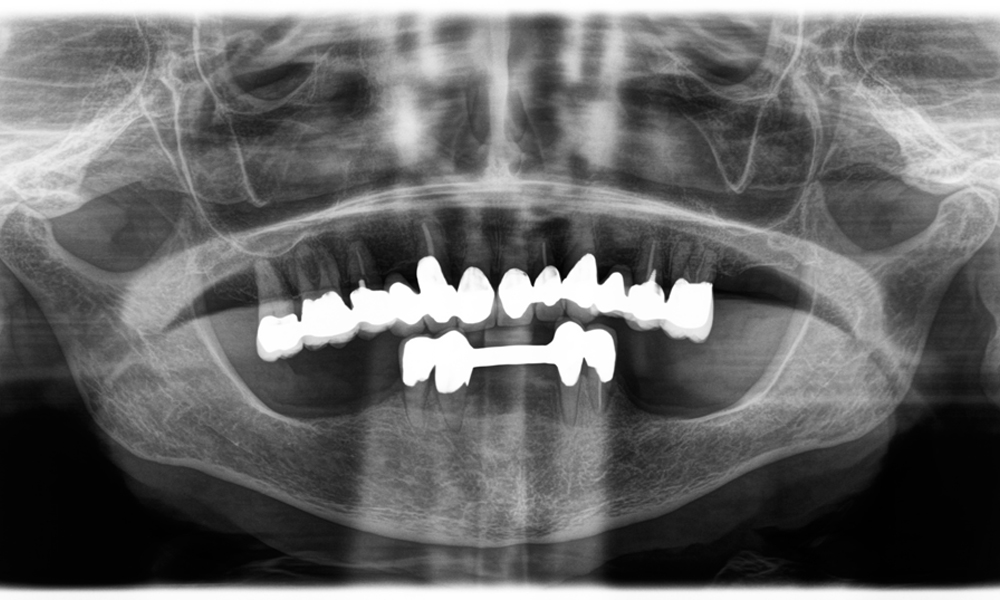

A second case highlighting the clinical capabilities of the Power Edition involved the replacement of a damaged zirconia crown in a 63-year-old patient. The patient presented with a chipped veneer on her 20-year-old zirconia crown on tooth 6. Despite the posterior location, the patient found the defect bothersome and requested a new restoration.

The Power Edition enabled precise sectioning, with the increased torque and enhanced cooling contributing to the controlled removal of the crown without significant material loss. The chucking system and enhanced torque proved to be essential in this process.

A x-ray, showing teeth and a zirconia crown, in front of a black background.

Figure 2: Replacement of a damaged zirconia crown: Precise removal and renewal of a damaged zirconia crown on tooth 6 with minimal material loss.